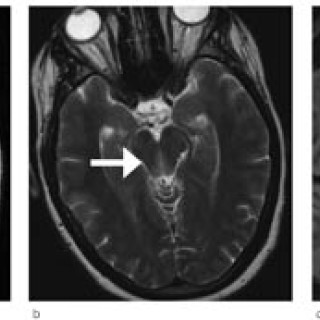

En 23 år gammel førstegangsgravid kvinne som fra tidligere stort sett var frisk, ble innlagt i lokalsykehus ved svangerskapslengde 22 uker + 2 dager, med en seks dagers sykehistorie med generell sykdomsfølelse, feber opptil 40 °C, kvalme, oppkast og anoreksi. I tillegg hadde hun fått økende ansiktsødemer, korsryggssmerter, hodepine og synsforstyrrelser. Svangerskapet hadde vært ukomplisert frem til det aktuelle. Hun var normotensiv. Blodprøvene viste kreatinin 236 µmol/l, karbamid 13 mmol/l, urat 410 µmol/l, leukocytter 15,0 · 10⁹/l, CRP 106 mg/l og trombocytter 86 · 10⁹/l. Leverprøvene var...